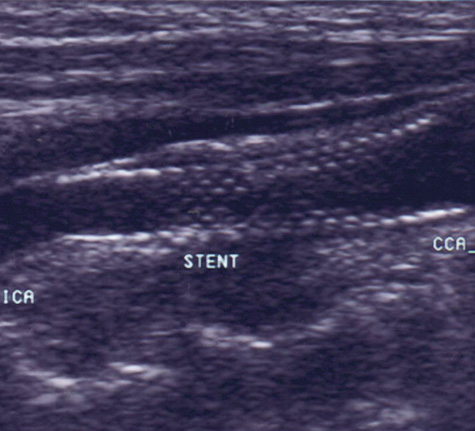

In the evaluation of extracranial large vessel disease, mainly carotid disease, ultrasound is the initial indicated study. It is commonly available, relatively inexpensive, and accurate. In addition, compared to other vascular imaging methods, it has the ability to directly image and characterize the plaque. Certain plaque characteristics may predict an increased risk of embolization. For example, the presence of an ulcer at the plaque surface may promote the formation of thrombus that can secondarily embolize, while a hypoechoic plaque, representing either intraplaque hemorrhage or a lipid-rich plaque, is associated with the potential for plaque destabilization.79,80 Carotid artery ultrasound has a sensitivity of 90% to 95% and specificity of 85% compared to catheter angiography.81 However, ultrasound may be unable to detect high-grade stenosis and mistakenly diagnose a carotid occlusion in 5% of cases. It is important to make this distinction as a patent vessel may be amenable to a revascularization procedure. Although power Doppler and echo-contrast agents may improve the odds of a correct diagnosis, for now it is standard practice to corroborate carotid occlusions with another imaging modality such as MRA, computed tomographic angiography (CTA), or conventional catheter angiography. MRA is an evolving technology comparable in accuracy to ultrasound, with the advantage of being able to image the distal carotid. In the past, there was a risk of overestimation of carotid stenosis by MRA, and beyond 70% stenosis, the absence of signal (flow gap) impeded adequate quantification of narrowing.82 Evolution in MRA technology and the use of contrast agents has improved the yield of this diagnostic method. Catheter angiography is the gold standard for carotid disease, but has inherent risks, with approximately 1% risk of stroke, although probably less in experienced centers. Figure 2 demonstrates the use of imaging technology in carotid disease.

Fig. 2. This 48-year-old diabetic man suddenly developed confusion and clumsiness of the right hand. On examination, he had inability to identify objects by touch and difficulty identifying the right from the left. A. Fluid attenuated inversion recovery (FLAIR) MRI shows a left parietal cortical infarct. Two potential embolic sources were noted: a left ventricular apical clot was seen on echocardiography from a presumed recent silent myocardial infarction, and ultrasound and subsequent angiography confirmed a significant left internal carotid stenosis. B: A 70% left internal carotid artery origin stenosis is shown on angiography. Monitoring both middle cerebral arteries with transcranial Doppler showed microembolic signals only over the left, suggesting that the carotid atherostenotic plaque was active or destabilized. C: An interruption (arrow) of the normal Doppler flow pattern of the middle cerebral artery is shown, representing a microembolic signal. The artery was stented rather than revascularized by endarterectomy because of the recent myocardial infarction. D: A patent revascularized carotid is revealed by ultrasound; note the struts of the stent.

Carotid angioplasty and stenting is a novel endovascular approach to revascularizing the carotid artery. As a technique, it is in its infancy, and catheter technology and distal protection devices to prevent periprocedural strokes are constantly evolving. To date, no randomized study has shown superiority of this technique over surgical endarterectomy in the average patient,83,84 although direct comparisons between endarterectomy, and angioplasty and stenting are currently underway.85 However, high-risk patients appear to do better with endovascular approaches.86 In the author's opinion, for now angioplasty and stenting should be reserved for symptomatic patients who cannot undergo surgery or generalized anesthesia because of cardiac or pulmonary conditions. Certain situations, such as radiation-induced arteriopathy, contralateral occlusion or high-grade stenosis, or contralateral vocal cord paralysis, are relative contraindications to endarterectomy; in their presence angioplasty and stenting is an appropriate therapeutic choice. An example of carotid stenting is shown in Figure 2.